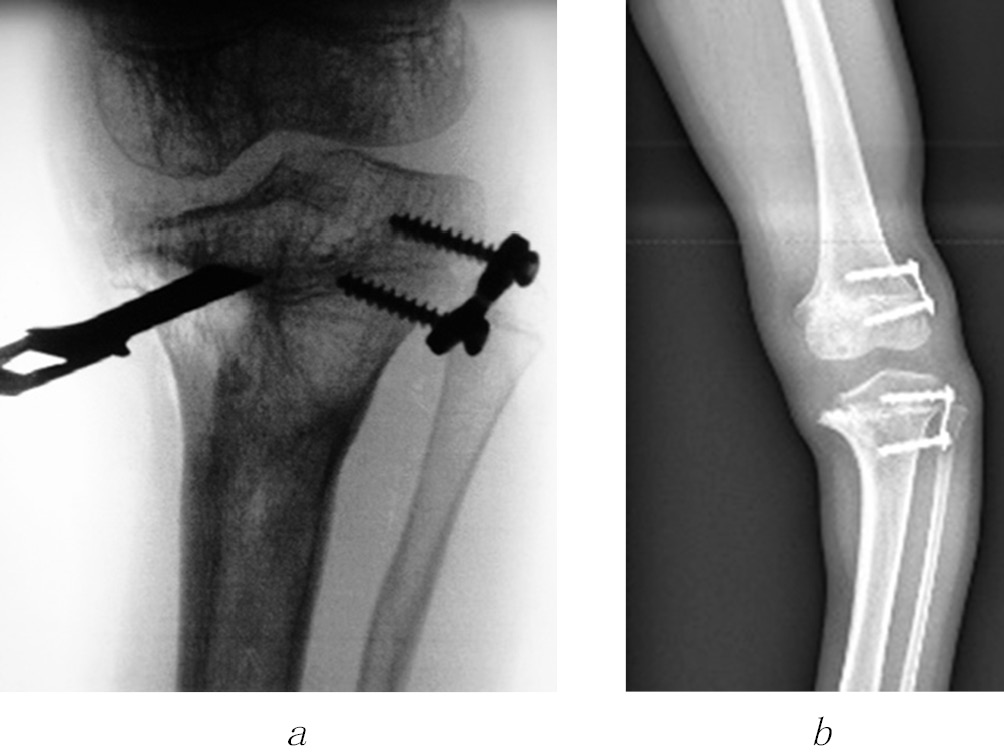

The shortening of the lower limb by 4 cm or more, the shoulder by 6 cm or more, and the forearm by 5 cm or more were considered an indication for surgical treatment, taking into account the age of the child. In the presence of angular deformities of the limb segments, accompanied by a shortening of 3 cm or more, one-stage correction of the length and shape of the limb segment by osteotomy was performed using compression-distraction osteosynthesis. At the final stage of treatment, to correct the multiplanar deformities of the bone metaphyses forming the knee and ankle joints, the Ortho-SUV reposition unit was used in three patients, which allowed to reduce the time and improve the quality of reposition (Fig. 1).

Fig. 1. Radiographs of patient G.’s lower extremities before (a) and during the correction of the shape and length of the right and left lower extremities using the Ortho-SUV reposition unit (b) and the standard layout of the Ilizarov apparatus (c)